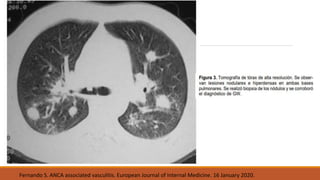

Las radiografías de tórax y la tomografía computarizada muestran uno

o múltiples nódulos unilaterales o bilaterales, excavados en la mitad de

los casos.